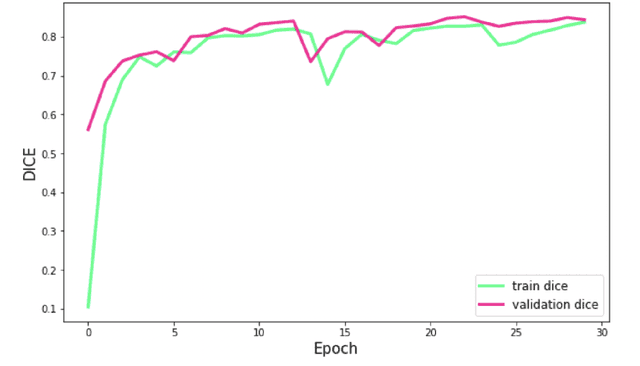

Lacunes of presumed vascular origin are fluid-filled cavities of between 3 - 15 mm in diameter, visible on T1 and FLAIR brain MRI. Quantification of lacunes relies on manual annotation or semi-automatic / interactive approaches; and almost no automatic methods exist for this task. In this work, we present a two-stage approach to segment lacunes of presumed vascular origin: (1) detection with Mask R-CNN followed by (2) segmentation with a U-Net CNN. Data originates from Task 3 of the "Where is VALDO?" challenge and consists of 40 training subjects. We report the mean DICE on the training set of 0.83 and on the validation set of 0.84. Source code is available at: https://github.com/hjkuijf/MixLacune . The docker container hjkuijf/mixlacune can be pulled from https://hub.docker.com/r/hjkuijf/mixlacune .